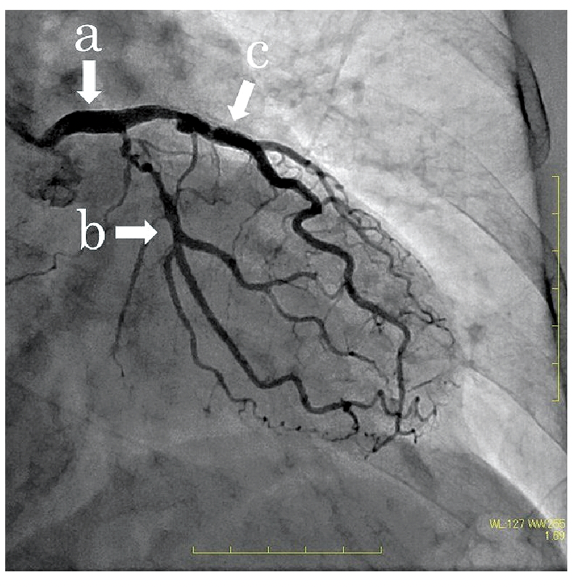

これは外科専門医試験の問題で、CRAかCAUさえ与えられていないという鬼問題。

とりあえずRAO。あとはCRAかCAUか。cからは中隔枝がいっぱいでてるように見える。

CRAだったらもうちょっと右上に全体的に寄るから、これはCAU。

ということは真ん中にあるbがCX。

やっぱりcがLAD。